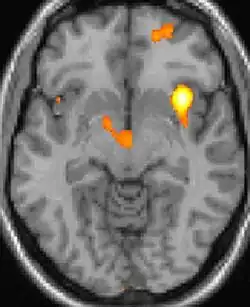

Positron emission tomography (PET) scans indicate the brain areas which are activated during attack only, compared to pain free periods. These pictures show brain areas that are active during pain in yellow/orange color (called "pain matrix"). The area in the center (in all three views) is activated only during cluster headaches. The bottom row voxel-based morphometry shows structural brain differences between individuals with and without CH; only a portion of the hypothalamus is different.[36]